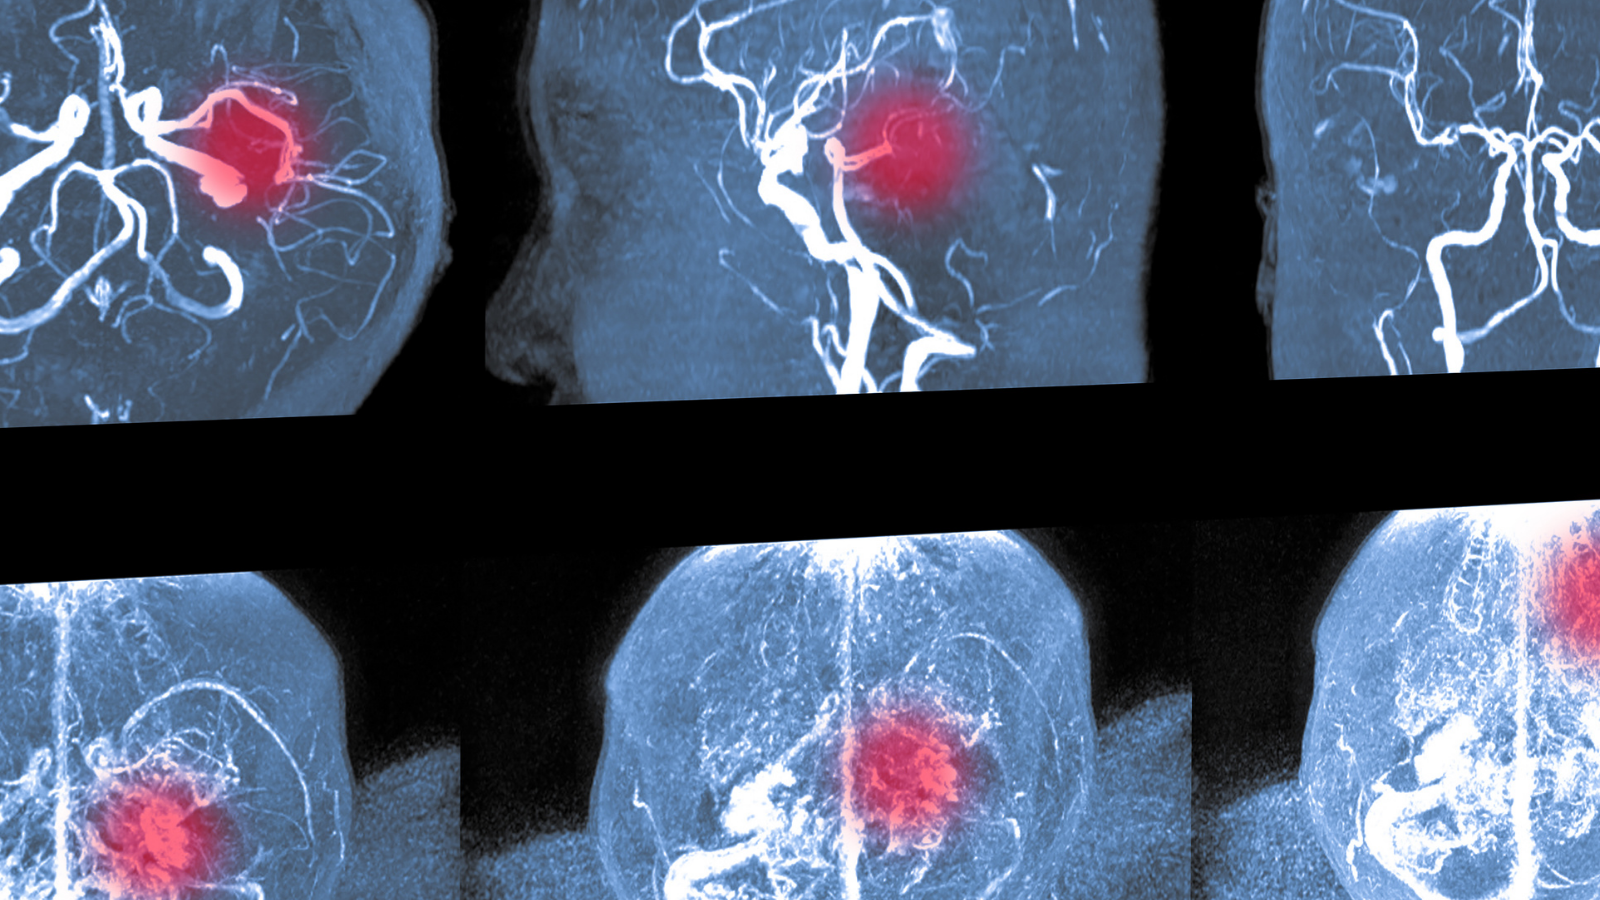

Trẻ sơ sinh bị xuất huyết não là một trong những biến chứng nguy hiểm nhất xảy ra trong hoặc sau khi sinh, đặc biệt ở trẻ sinh non. Tình trạng này nếu không được phát hiện và điều trị kịp thời có thể để lại di chứng về vận động, trí tuệ hoặc thậm chí đe dọa tính mạng.

Đây là hiện tượng mạch máu trong não bị vỡ hoặc rò rỉ, khiến máu tràn vào mô não hoặc các khoang quanh não. Đây là một dạng chấn thương não đặc trưng ở trẻ sinh non (dưới 32 tuần tuổi thai) hoặc trẻ gặp khó khăn khi sinh.

- Xuất huyết trong não thất (Intraventricular Hemorrhage - IVH): Máu chảy vào hệ thống não thất, có thể gây tắc nghẽn dòng lưu thông dịch não tủy.

- Xuất huyết nhu mô não: Dạng nặng nhất, gây tổn thương trực tiếp đến mô thần kinh.